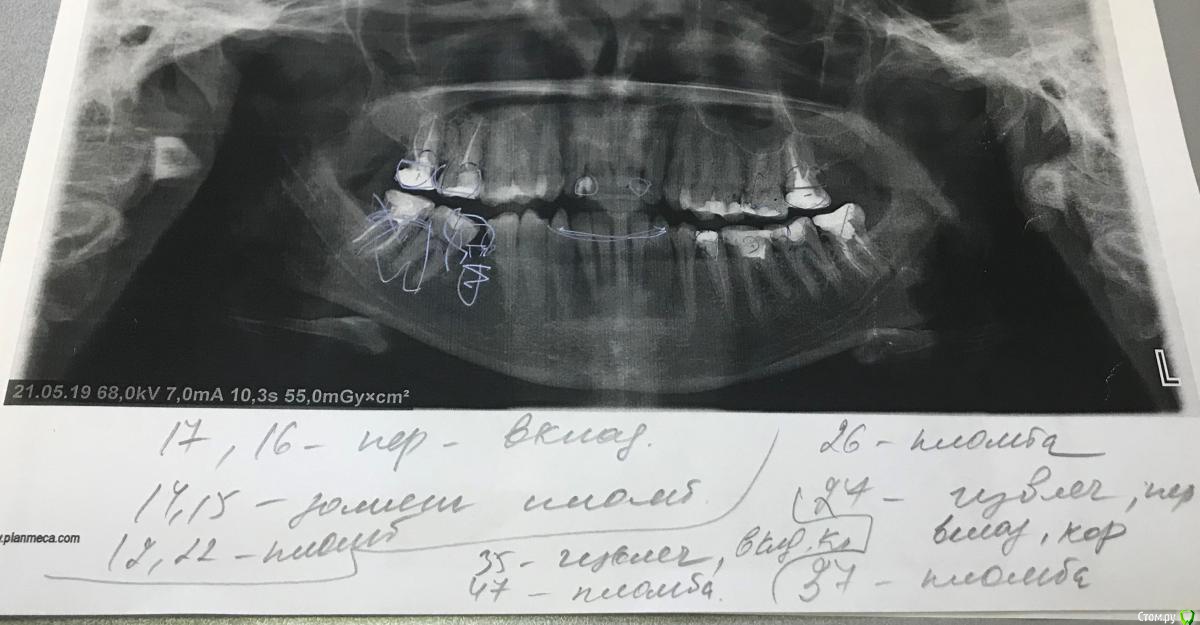

Верхних 8к нет, нижние стоят

6го нижнего нет с 10 лет, в последствии планируется имплантация.

Куча работы по санации.

post-57831-0-13521200-1559162307_thumb.jpg post-57831-0-63906900-1559162316_thumb.jpg post-57831-0-91130000-1559162581_thumb.jpeg post-57831-0-53729100-1559162664_thumb.jpeg post-57831-0-75857000-1559162676_thumb.jpg